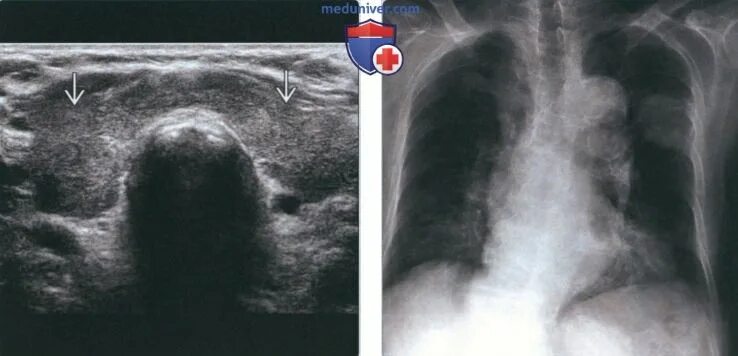

Лучевая терапия метастазов в лимфоузлах